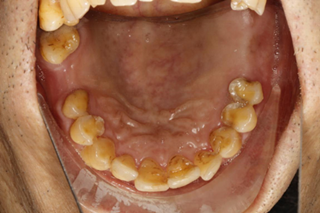

牙齿情况:口内牙齿松动,牙齿根尖有炎症,多颗牙齿缺失

谢铭勋牙齿情况

经过检查,郑苍尚院长发现谢铭勋口内上颌缺牙3颗,下颌缺牙6颗,余牙松动,牙根尖伴有炎症,且因长期牙周疾病,牙槽骨有中度萎缩,最好的治疗方案就是选择种植牙。根据谢铭勋口内的情况,郑苍尚院长为他量身定制了麦芽口腔微创微痛种植牙技术。

谢铭勋口内牙齿情况